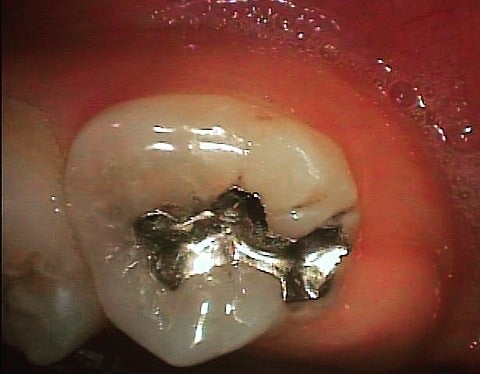

<銀歯を外した状態>

▶︎やはり広範囲で虫歯が隠れていました。